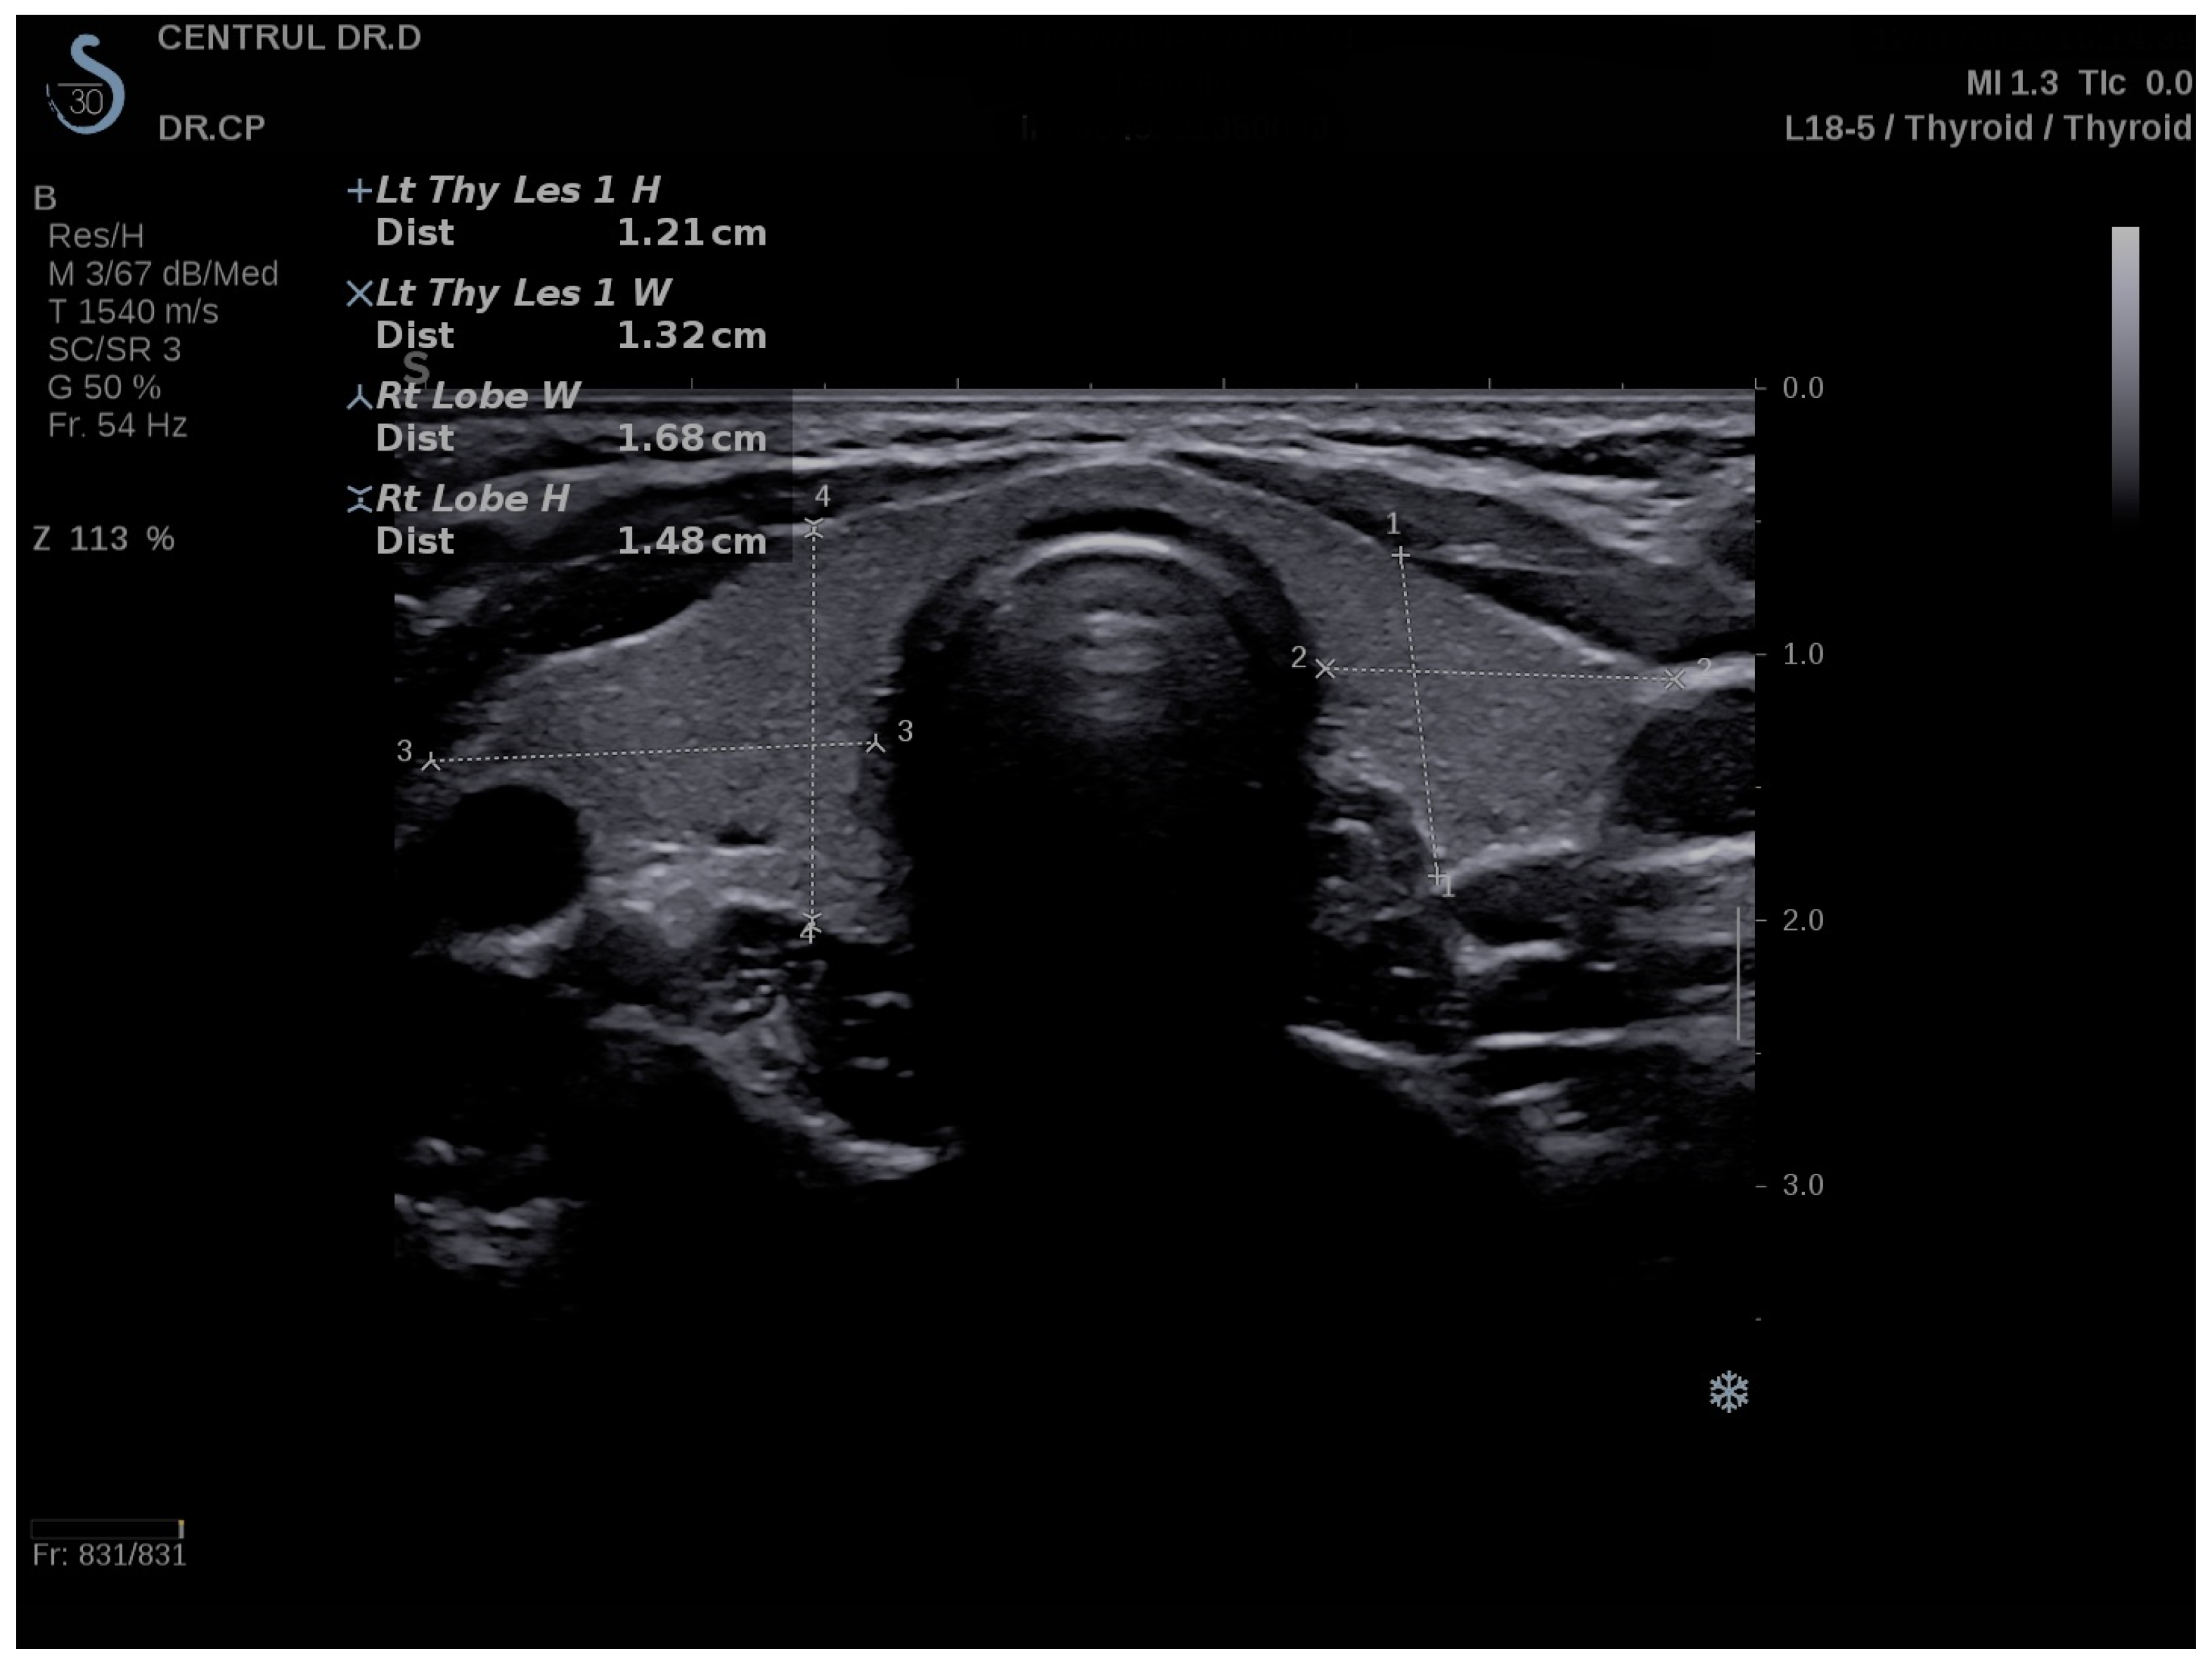

2.4. Conventional Ultrasound and Elastography Examination